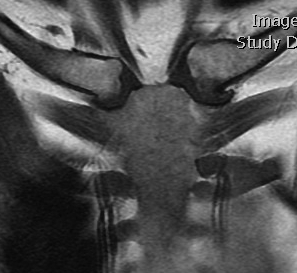

CT

Sternoclavicular Hyperostosis

Bilateral condition

- ossification of sternoclavicular ligaments

- may lead to solid ossification with restriction of shoulder motion